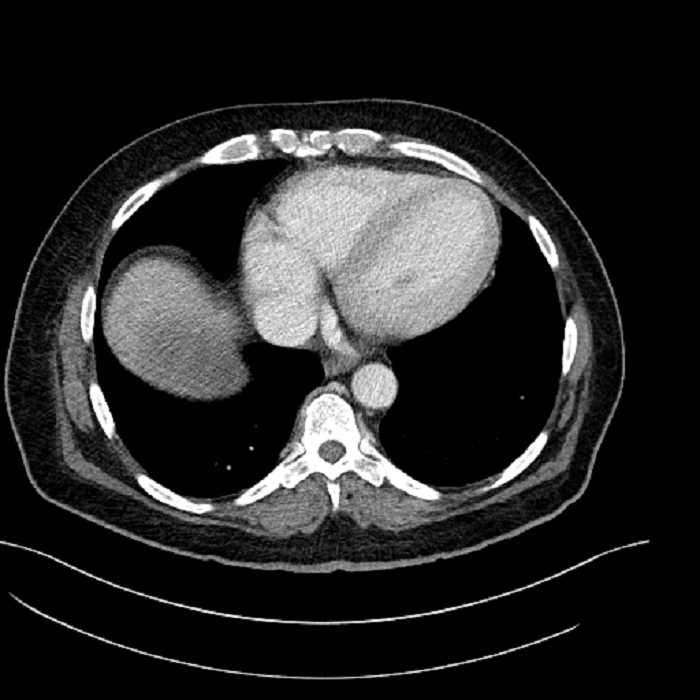

• Mild cardiomegaly

• Mild dependent atelectasis

• Large fluid density structure in hepatic segments 7 and 8 measuring 10 x 7 x 7 cm with internal septation and circumferential ill-defined low density compatible with edema

Acute sigmoid diverticulitis complicated by a small contained perforation and a large abscess in the right hepatic lobe. Additional small subcapsular abscesses along the anterior margin of the left hepatic lobe.

• The classic CT imaging appearance is a double target sign with internal low density surrounded by an internal enhancing rim (capsule) and a low density external rim (edema)

Hepatic abscess showing the double target sign with low density internally surrounded by a thin inner enhancing rim (red arrow) and ill-defined outer low density rim (yellow arrow). Blue arrow indicates an internal septation. Red arrows: additional smaller subcapsular abscesses. Red arrow: focal contained perforation associated with diverticulitis.